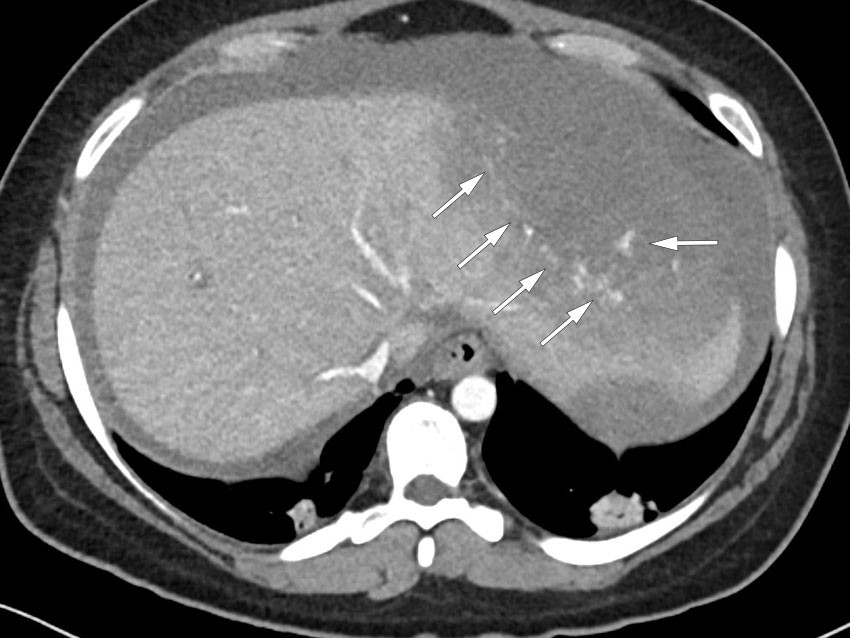

CT-bildet av abdomen viser en spontan leverruptur hos en pasient med HELLP-syndrom, som karakteriseres av massiv hemolyse, forhøyede leverenzymer og blodplatemangel (1). Bildet viser en koronal reformatering av abdomen i portovenøs kontrastfase med kontrastoppladning i intakt leverparenkym, hvor rikelig gjenværende kontrast i det arterielle kretsløpet kan forklares av reduksjon av hjertets minuttvolum som følge av lavt blodvolum og lavt blodtrykk.

CT-undersøkelse av abdomen (arteriell og portovenøs kontrastfase) viste et 8 × 14 cm stort lavattenuerende område fortil i venstre leverlapp og en væskebrem med høy attenuasjon rundt leveren, tolket som spontan leverruptur og leverblødning med subkapsulært hematom. Små høyattenuerende områder i leverparenkymet i arteriell kontrastfase, som ble større i den portovenøse fasen, ble tolket som tegn på ekstravasering av kontrastmiddel og pågående leverblødning.